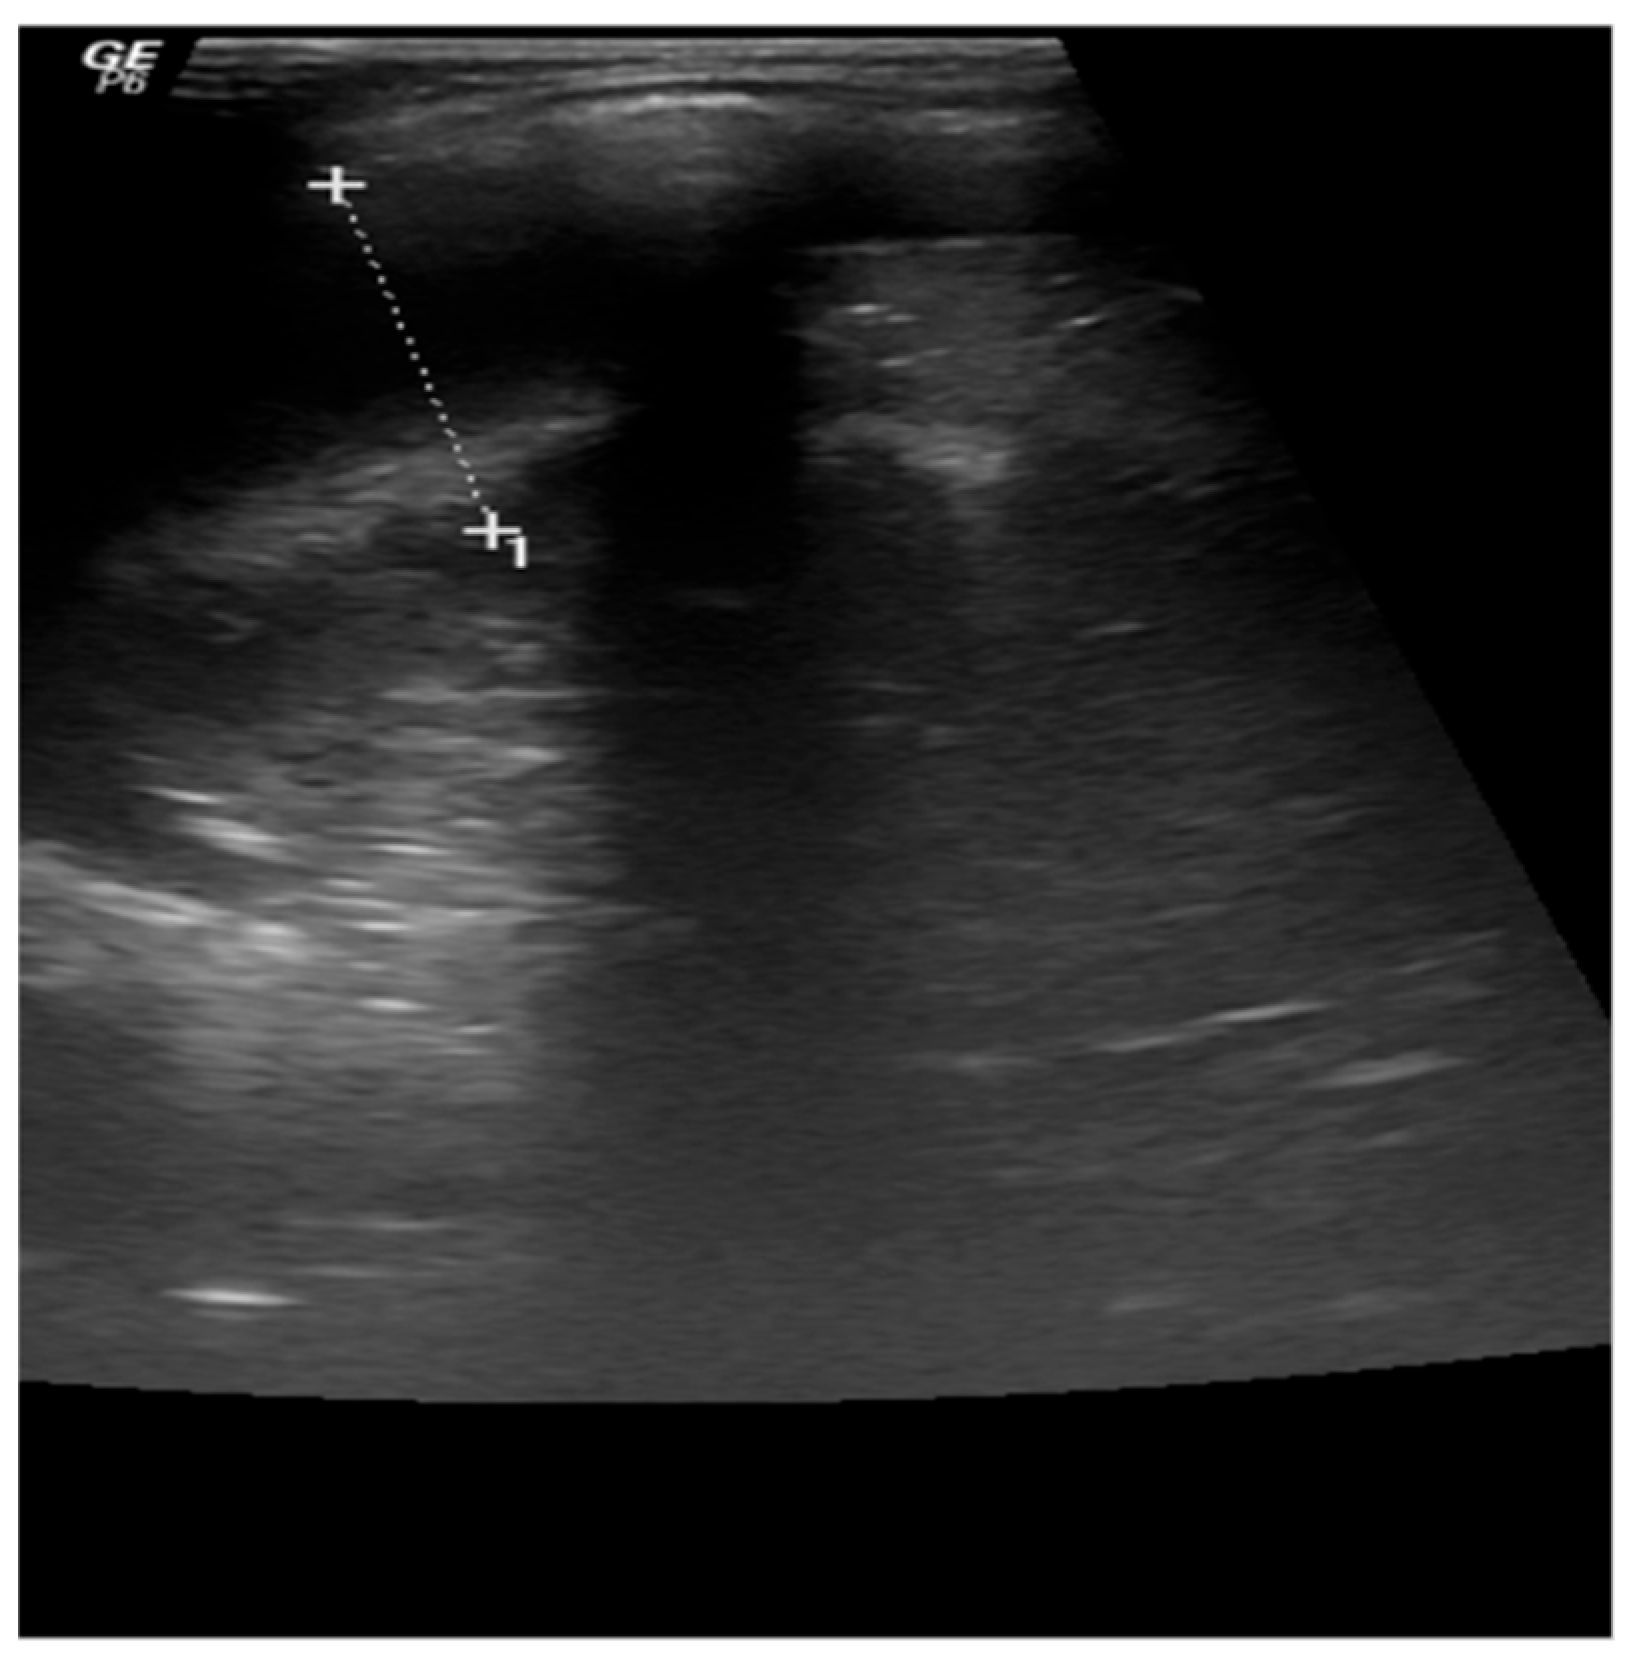

Chest X-ray revealed massive opacity of the right hemithorax, left upper lobe consolidation, and left perihilar and basal infiltrate (Figure 3). Chest ultrasound showed pleural effusion of the right hemithorax of 2.5 cm, right upper and lower lobe consolidation with air bronchogram (Figure 4).

Figure 4.

A 15-month-old female infant with hemophagocytic lymphohistiocytosis: thoracic ultrasound showing right-sided pleurisy in medium quantity—2.5 cm.